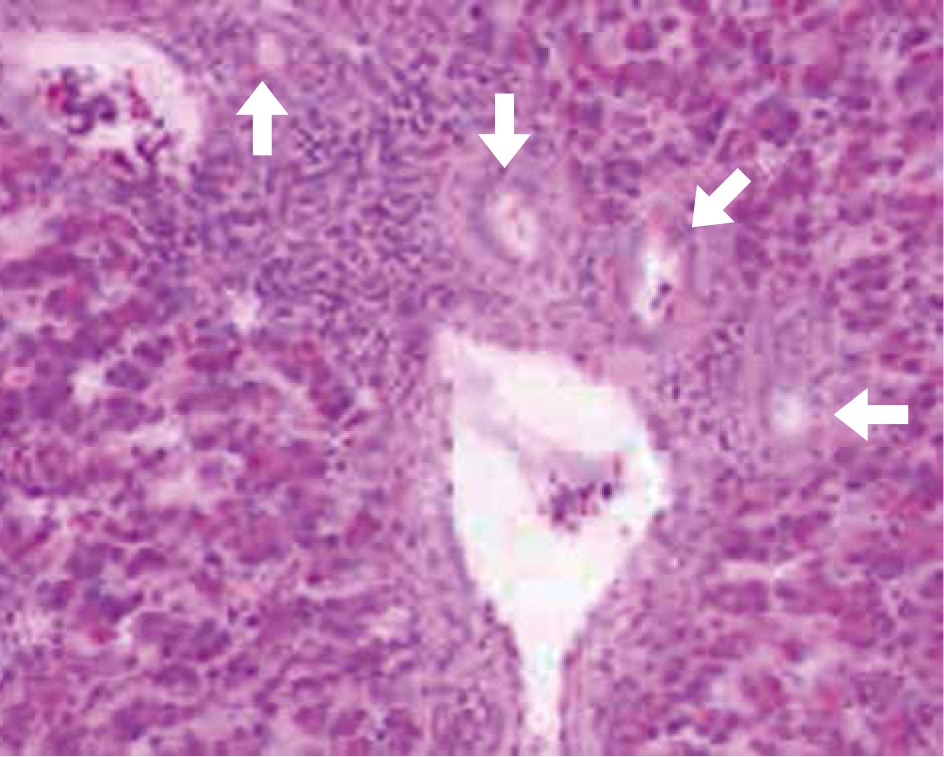

The characteristics of the studied patients are presented in Table 1. Histopathological features were observed in all liver specimens including the presence of lymphoid aggregation in portal tracts, variable degrees of steatosis and bile duct proliferation as shown in Figures 2 and 3. According to the METAVIR scoring system in regards to the fibrosis stage, 12 (48%) patients in group A showed F1, 12 (48%) patients showed F2 and only one (4%) patient showed F3. Patients in group B were found to have a significant increase in the fibrosis stage, where six (24%) showed F1, 12 (48%) showed F2 and seven (28%) patients showed F3.

Fig. 3

Peri-portal fibrosis extending towards neighbouring portal triad and into the lobules (surrounded with arrows)